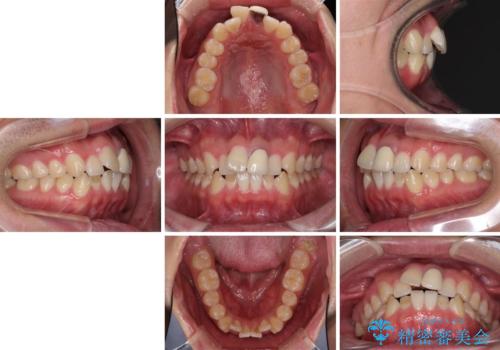

- 前歯の歯並びと不自然な色をした前歯のクラウンを気にして来院された患者様です。

上下前歯の歯列不正はインビザラインにより歯列を整え、その後に、前歯をオーダーメイドタイプのオールセラミッククラウンにて補綴治療することとしました。

初診時には、歯並びを整えることのみを検討されていましたが、歯列が整うにつれて不自然な色合いが気になるようになり、矯正治療を行ってから補綴治療をする計画を受け入れてくださいました。

口元の印象が明るく変わり、患者様には大変満足していただきました。